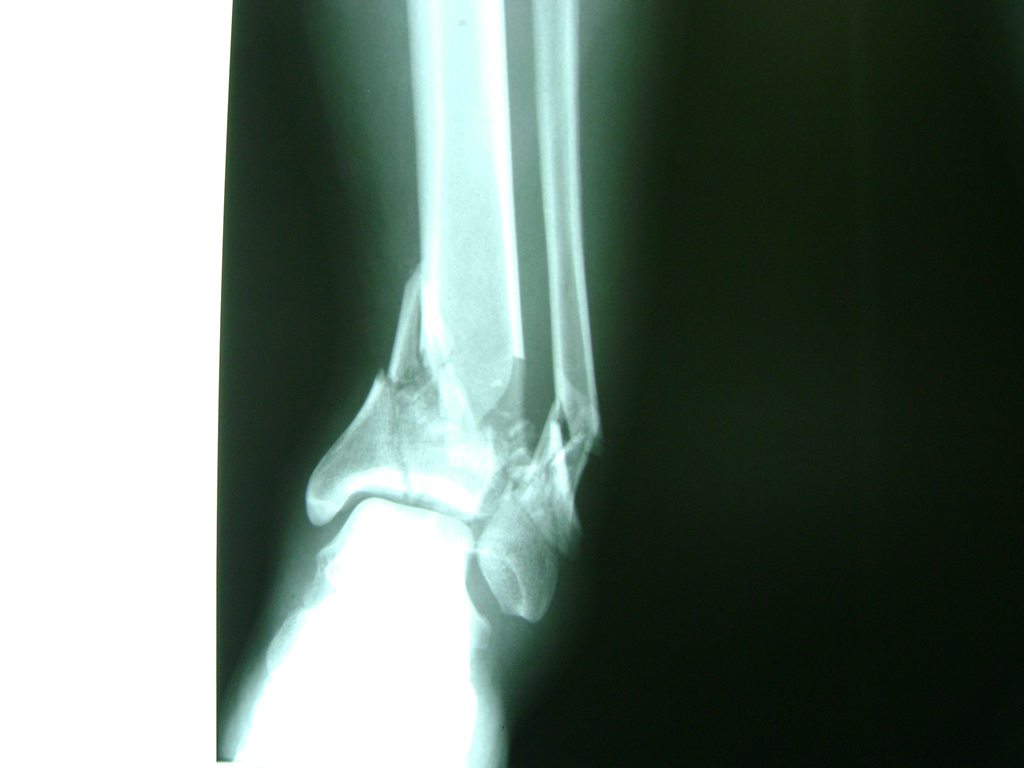

Una fractura de tobillo es la rotura de uno o más de los huesos del tobillo. Estas fracturas pueden ser:

Algunas fracturas de tobillo pueden requerir cirugía si:

- Los extremos de los huesos están desalineados entre sí (desplazados).

- La fractura se extiende hasta la articulación del tobillo (fractura intra-articular).

- Los tendones o ligamentos (tejidos que sujetan los músculos y los huesos entre sí) están rotos.